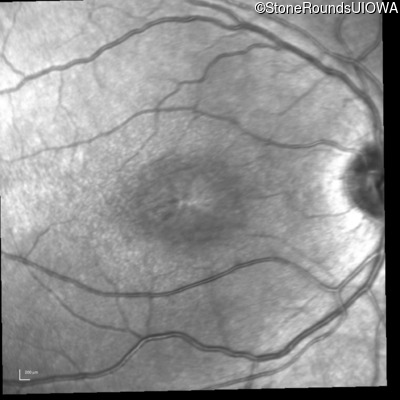

Infrared Fundus Photograph - Right - 20/63 -2

Exemplar

Infrared Fundus Photograph - Left - 20/50 -2